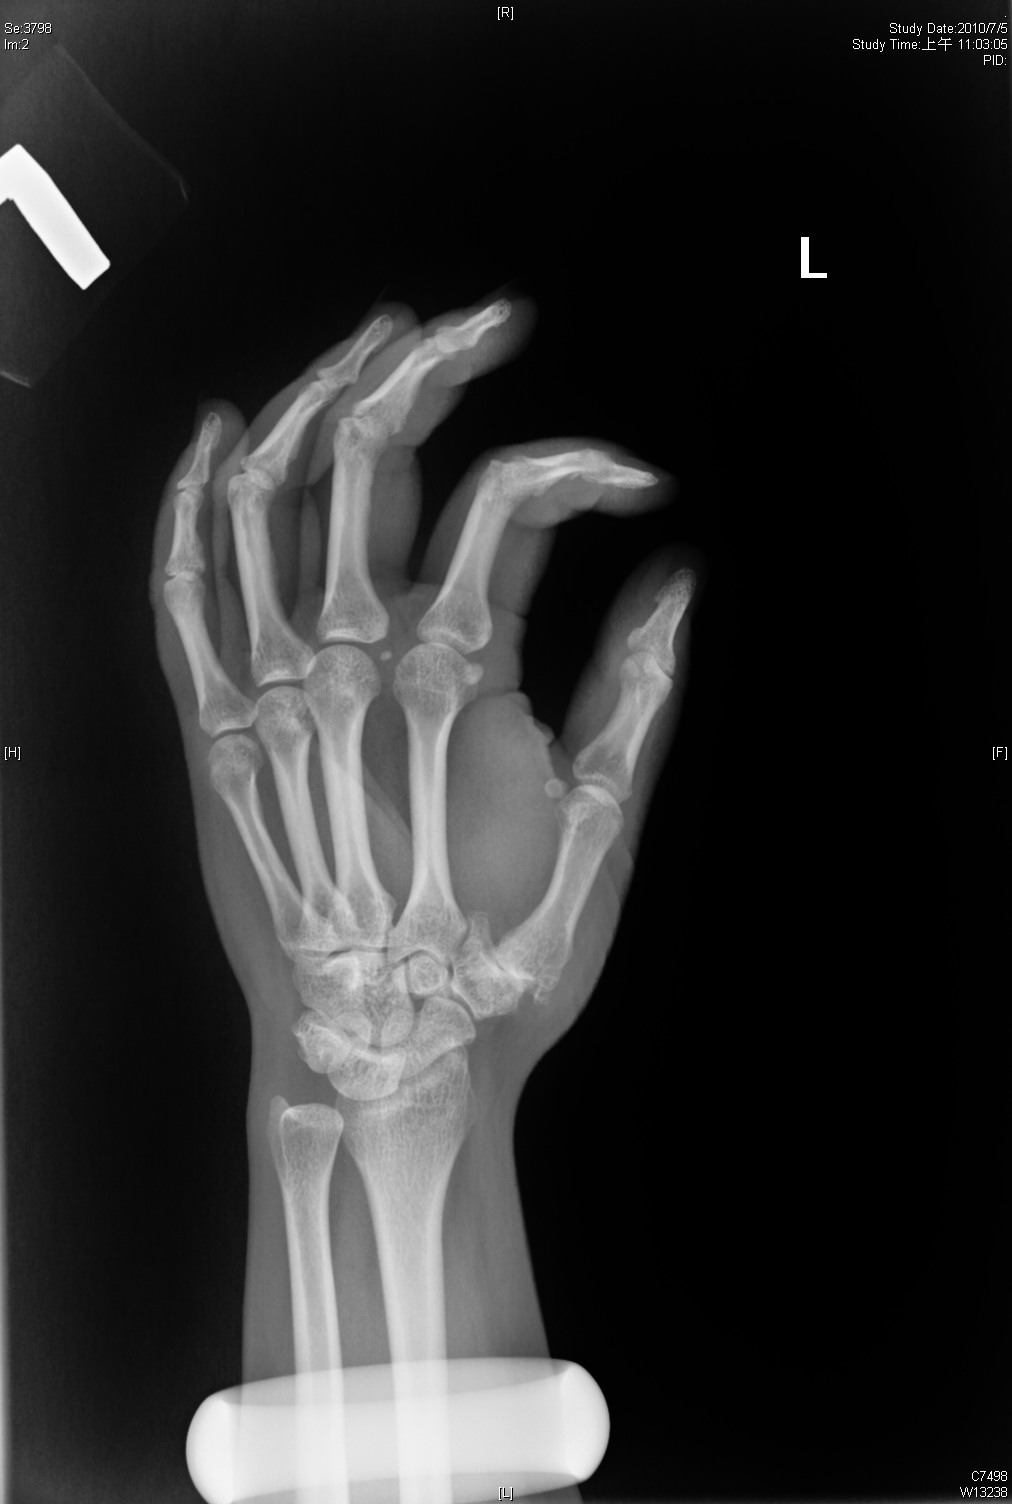

(A) Preoperative radiograph showing the first CMC joint subluxation in... Download Scientific Basal Joint Subluxation The first thing you may notice is swelling and. The symptoms of basal thumb arthritis are distinct, and as soon as you think you may have an issue in the joint, you should seek medical attention. The key principle is that each of the separate joints within the thumb basal joint with arthritis needs to be addressed along with the.. Basal Joint Subluxation.